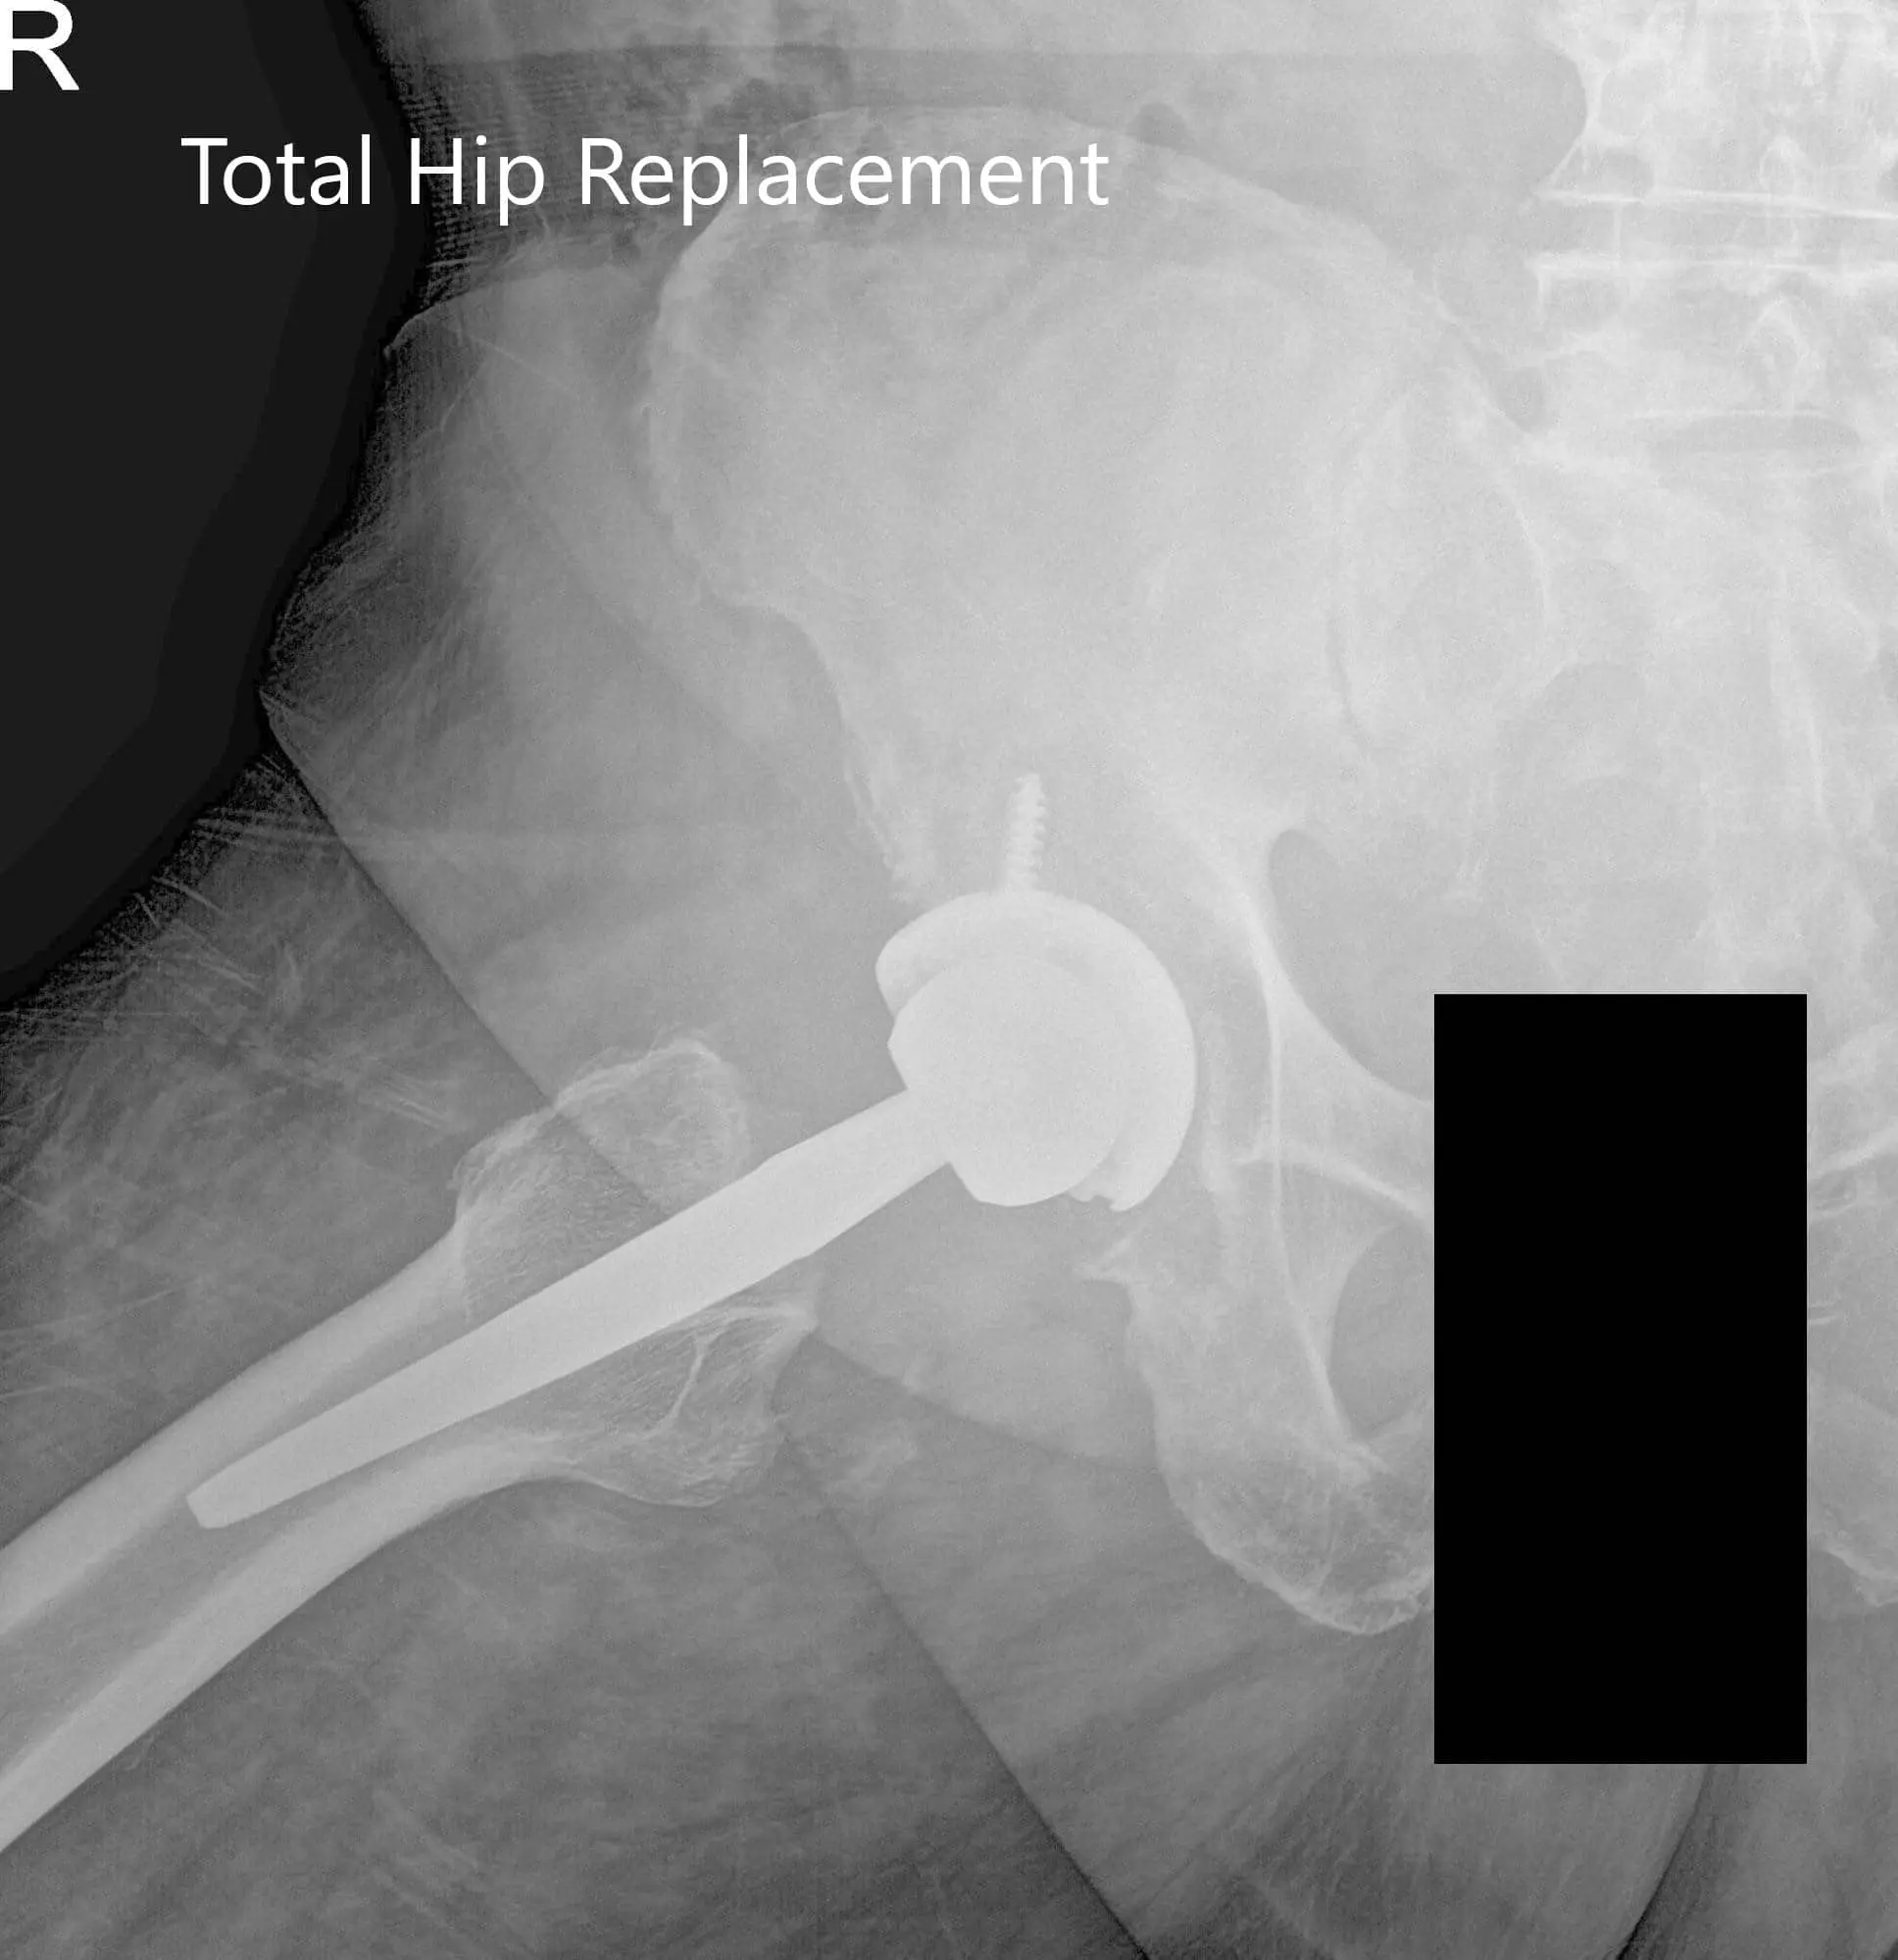

Preoperative X-ray images showing AP and frog-leg lateral view of the right hip - img 2

Preoperative X-ray images showing AP and frog-leg lateral view of the right hip